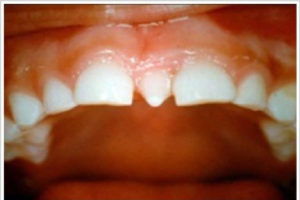

- Gigi Berlebih (Supernumerary Teeth)

Supernumerary teeth adalah gigi yang berkembang melebihi jumlah normal, dan gigi yang berkembang tersebut dapat normal secara morfologis, atau abnormal. Supernumerary teeth yang terletak diantara dua gigi depan atas disebut mesiodens. Faktor penyebabnya berasal dari herediter atau keturunan.

Jika anak mengalami hal ini, maka orangtua tidak perlu kuatir. Periksakan anak ke dokter gigi, biasanya dokter kana melakukan rontgen panoramik terlebih dahulu untuk memastikan gigi berlebih dan benih gigi tetap lainnya. Tindakan selanjutnya biasanya adalah mencabut gigi berlebih.